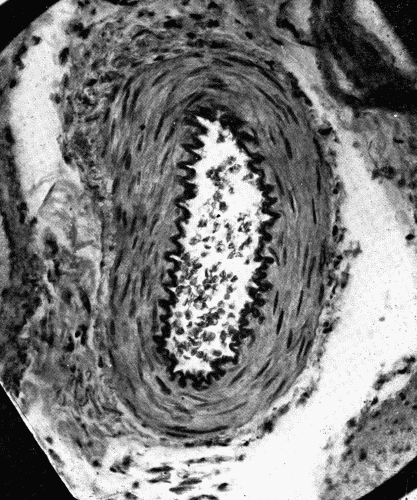

Thayer and Fabyan, in an examination of the radial artery from birth to old age, found that, in general, the artery strengthens itself, as more strain is thrown upon it, by new elastica in the intima and connective tissue in the media and adventitia. Up to the third decade there is only[35] a strengthening of the media and adventitia. During the third and fourth decades there is also distinct connective tissue thickening in the intima. "In other words, the strain has begun to tell upon the vessel wall, and the yielding tube fortifies itself by the connective tissue thickening of the intima and to a lesser extent of the media." By the fifth decade the connective tissue deposits in the intima are marked, there is an increase of fibrous tissue upon the medial side of the intima and, in lesser degree, throughout the media. "Finally, in these sclerotic vessels degenerative changes set in, which are somewhat different from those seen in the larger arteries, consisting, as they do, of local areas of coagulation necrosis with calcification, especially marked in the deep layers of the connective tissue thickenings of the intima, and in the muscle fibers of the media, particularly opposite these points. These changes may ... go on to actual bone formation." The mesenteric artery differs in some respects from the radial, but in the main, the changes brought about by age are the same. Thayer and Fabyan note two striking points of difference: "(1) calcification is apparently much less frequent than in the radials; (2) in several cases plaques were seen with fatty softening of the deeper layers of the intima and superficial proliferation—a picture which we have never seen in the radial." (See Fig. 2.)

Fig. 2.—Cross section of a coronary artery, ×50, showing nodular sclerosis. Note the heaping up of cells in the intima, the fracture of the elastica, and the destruction of the media beneath the nodule. The primary lesion evidently was in the media. The thickened intima is the effort on the part of nature to heal the breach. At such places as shown here aneurysms may form. (Microphotograph.) Fig. 2.—Cross section of a coronary artery, ×50, showing nodular sclerosis. Note the heaping up of cells in the intima, the fracture of the elastica, and the destruction of the media beneath the nodule. The primary lesion evidently was in the media. The thickened intima is the effort on the part of nature to heal the breach. At such places as shown here aneurysms may form. (Microphotograph.)